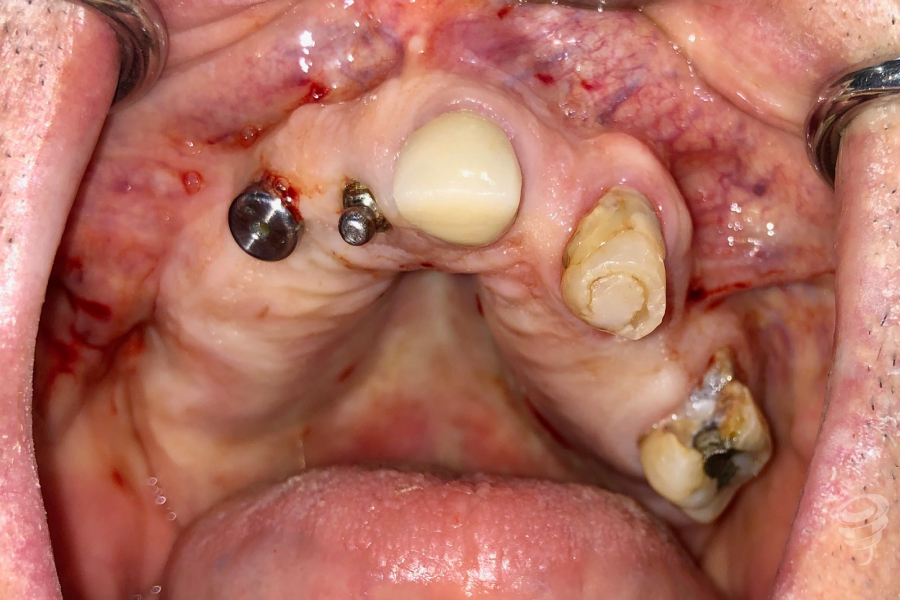

Protocolo en pacientes periodontales severos: Edentación + Implantes cigomáticos y convencionales inmediatos + Carga inmediata (CBCT y aspecto intraoperatorio de la cresta maxilar). (Imagen 14-25)

Hoy en día este protocolo nos permite abordar casos con enfermedad periodontal severa en pacientes con poco volumen óseo en sectores posteriores, que no quieren estar sin dientes, con protocolos de implantes inmediatos a extracción y carga inmediata con excelentes resultados a largo plazo. (Imagen 14-25)

Imagen 17 – Post-Edentación Completa

Imagen 18 – Cresta ósea Post-Edentación